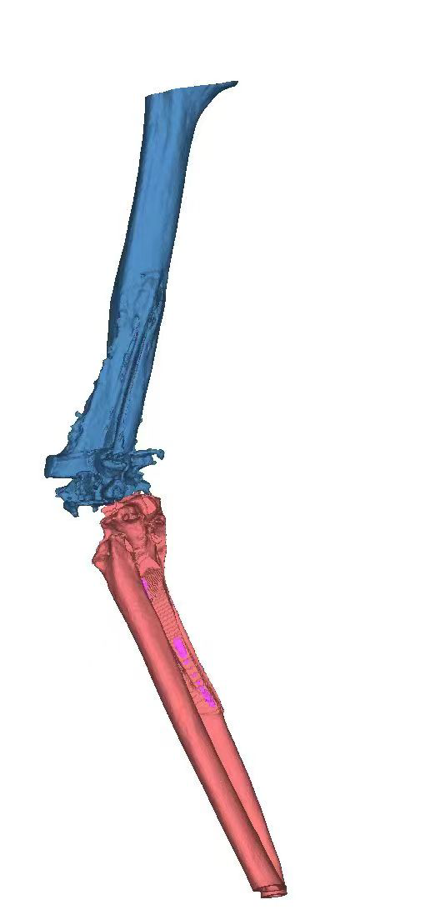

与其他人工关节置换术相比,全肘关节置换术在设计和手术技术上要求更高。肘关节的复杂运动特性使得术后假体活动和稳定性的控制成为一大挑战。此外,假体在各种体位和活动中的松动、断裂和磨损风险,对手术医师的操作准确性与熟练度提出了严格要求。该患者术前肘关节假体肱骨侧及尺骨侧均几乎穿出骨皮质,髓腔形态异常,为确保手术成功,关节与足踝病区团队完善术前讨论,为该患者设计了个性化的3D打印肘关节假体,并提前模拟了手术假体安装过程。在王坤正教授的指导下,杨佩教授、王春生副主任医师经过精细操作,最终使这一例复杂肘关节置换术最终成功实施,使患者可以更快地恢复肘关节功能,进行正常的日常生活活动,提高生活质量。